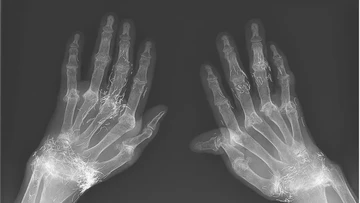

Jakarta - Belum lama ini heboh gambar rontgen penemuan benang 'susuk' emas di dalam tubuh seorang pasien di Korea Selatan.